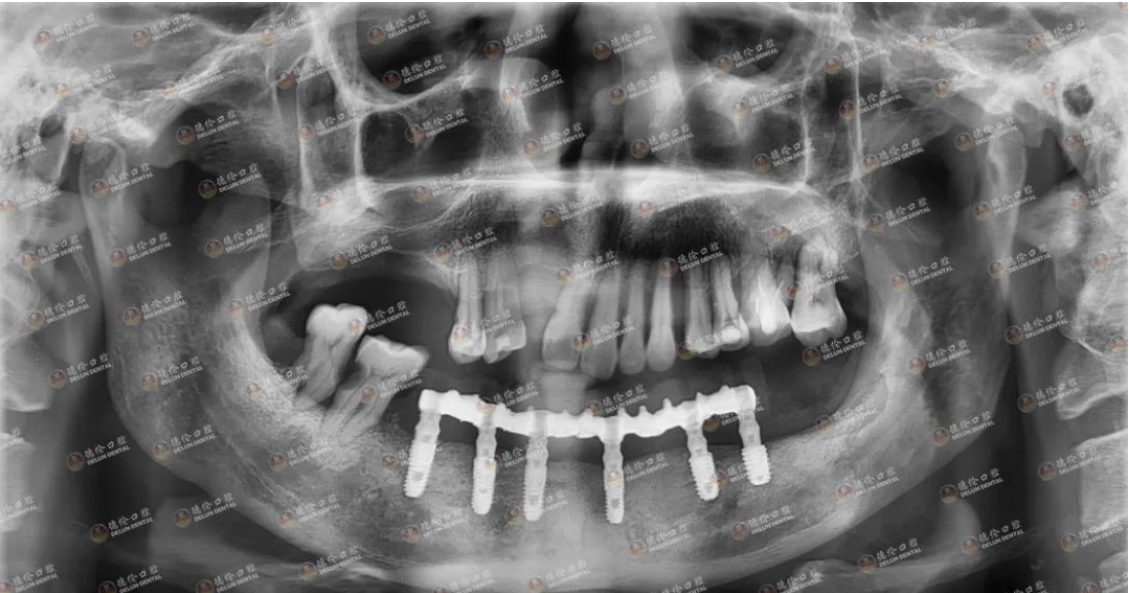

2021年4月,一位来自广州天河区的60多岁老人前来德伦寻求帮助。他自述在其他医院种牙失败,种了六颗牙,现在掉了四颗,感觉自己在种牙上花了很多冤枉钱和时间,走了很多弯路,精疲力尽,受罪不说还赔上了健康。患者来到德伦口腔,接待他的是德伦口腔东风总院种植科罗朝阳副主任。经过罗主任对患者全身状态评估,口内状况及影像数据的检查,告知患者符合再种植条件,并给出了多种种植修复方案,患者知情同意,选择数字化导板种植,埋入愈合,3个月后二期修复,咬合重建,金塑桥过度,最终钛支架和烤瓷牙固定种植义齿修复方案,帮助患者逐步恢复口腔功能及身体健康。